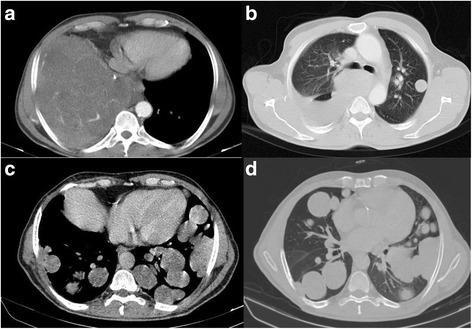

The patient presented with a case of classic biphasic pulmonary blastoma (CBPB) with hypoglycemia. Chest CT scan showed 2 huge masses in the right hemi-thorax and multiple smaller masses located in the left hemi-thorax. The patient underwent surgery, and was referred to an oncologist for adjuvant therapy.

该患者患有伴有低血糖症的经典双相性肺母细胞瘤(CBPB)。胸部CT扫描显示右半胸有2个巨大肿块,左半胸有多个较小肿块。患者接受了手术,并转诊给肿瘤学家进行辅助治疗。